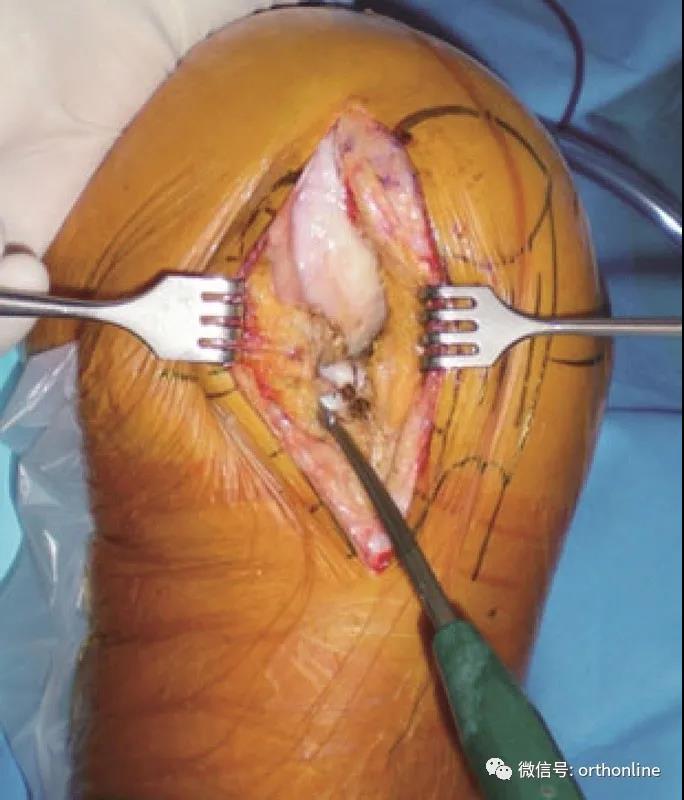

放置股骨截骨模板

股骨截骨模板放置在股骨外髁中心并垂直于胫骨截面

截骨后放入试模,测试轨迹